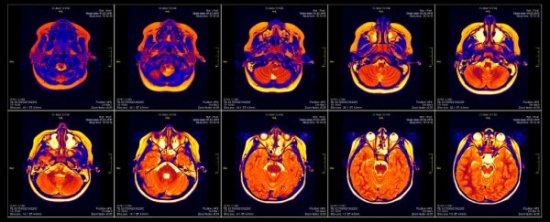

- Como hemos visto, las técnicas del neuromarketing requieren de una aparatosa maquinaria alrededor de nuestra cabeza, imposible de ignorar